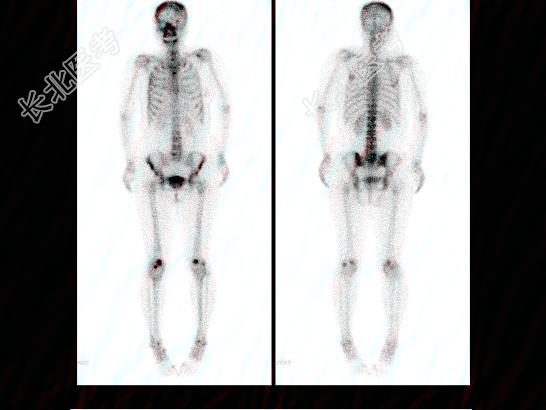

- 多项选择题右乳癌根治术后5年,无明显不适, 血清CA153正常,行全身骨显像如图, 可能的诊断是 ( )

A、多发骨转移瘤

B、骨质疏松

C、腰椎退行性改变

D、腰4、5骨转移瘤

E、大致正常的骨影像